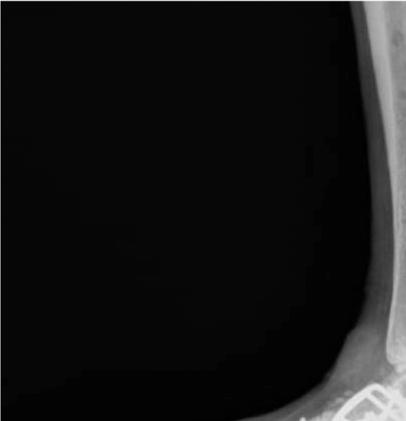

4fordatacollectiontools.)Thrombotic eventswerecollectedduringindexhospitalizationandat30 and90daysafterdischarge.Wedefinedthromboticeventsas deepveinthrombosis(DVT),pulmonaryembolism(PE), ischemicstroke,myocardialinfarction,orotherarterialor venousthromboembolicevents.Doortoneedletimewas definedastimefromhospitalpresentationtoreceiptof reversalagent.OnsettoCTtimewascalculatedusingthe differencebetweeninitialCTandtimeofbleedingonset, wheretheybothexisted;onsettoCTtimefortheremainder ofcaseswasdeterminedbycombiningcategoricalonsetto presentationtime(<6,6–12,12–24,24–48,and >48hours),

usingthemediantimeforeachcategory,withdoortoCT time.Wedefinedallstudydataandvariablespriorto initiatingthestudyandtrainedourdataabstractorsusinga libraryofdefinitions(see Supplement1).Weperiodically monitoreddatacollectionandprovidedfeedbacktothedata abstractorsduringandafterdatacollectionandentry regardingmissing,conflicting,orobviouslyerroneousdata. Thenumberofdataabstractorsateachinstitutionvaried from1–3.Thedataabstracterswerenotblindedtotherapy.

Outcomes

Wedevelopedallstudyoutcomesapriori.Theprimary outcomeswerepresenceofestimatedtimesfromlastdoseof FXa-Iandtimefrombleedingonsettoadministrationof 4F-PCCorandexanetalfa.Secondaryoutcomeswere hemostaticefficacyasdefinedbytheANEXXA-4criteria,23 survivaltohospitaldischarge,thromboticeventsduringthe indexhospitalizationandat30and90days,andrebleeding eventssuchasICH,rectalbleeding,melena,orhematemesis.

DataAnalysis

Weuseddescriptivestatisticstosummarizethedata. Categoricaldataarepresentedasnumbersorpercentages andcomparedbetweengroupsusingchi-squareorFisher exacttestsasappropriate.Continuousvariablesare presentedwithmeansandstandarddeviationsormedians andinterquartileranges(IQR)basedontheirdistribution andcomparedwith t -testsortheMann-WhitneyUtests,as appropriate.Becausethiswasapilotstudy,noformalsample sizecalculationwasperformed.Wechosetoinclude25 patientsineachofthefourstudysubgroups:ICHtreated withandexanetalfa;ICHtreatedwith4F-PCC;GIBtreated withandexanetalfa,andGIBtreatedwith4F-PCC.An exploratoryPSMmodelwasconstructedtoestimatetheodds ofexcellent/goodhemostaticefficacyinpatientstreatedwith andexanetalfaor4F-PCCadjustingforage,gender, comorbidities,timefromlastdoseofFXa-I,time frombleedonsettotreatment,andindication foranticoagulation.